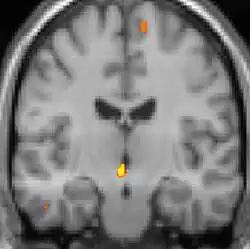

| Voxel-based morphometry shows brain area structural differences. | ||

Positron emission tomography (PET) scans indicate the brain areas which are activated during attack only, compared to pain free periods. These pictures show brain areas that are active during pain in yellow/orange color (called "pain matrix"). The area in the center (in all three views) is activated only during cluster headaches. The bottom row voxel-based morphometry shows structural brain differences between individuals with and without CH; only a portion of the hypothalamus is different.[37]